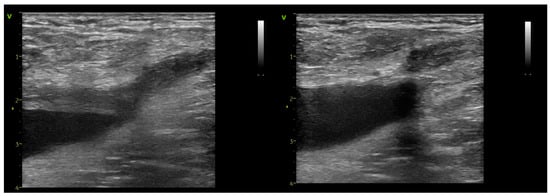

2. Materials and Methods